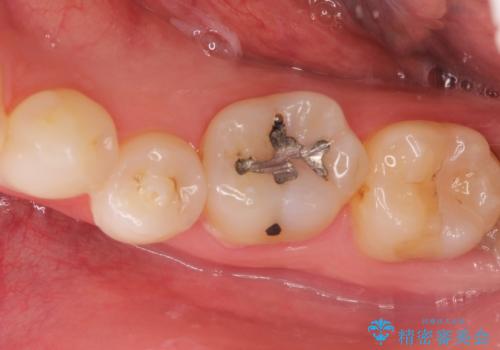

メタルフリー セラミックインレー

- メタルフリーの治療を希望されて来院されました。

セラミックインレーの治療を2回の来院で終了しております

e-max プレスインレーにて修復治療を行っているため適合性及び審美性の高い治療を行うことができます